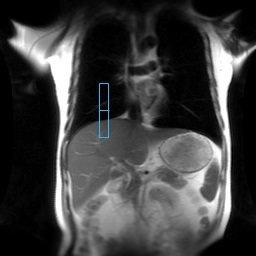

Figure 6. On the coronal localizer, the tracker center is placed over the dome of the liver

- The tracker position is automatically placed on the localizer based on the Auto Tracker Placement post-processing application.